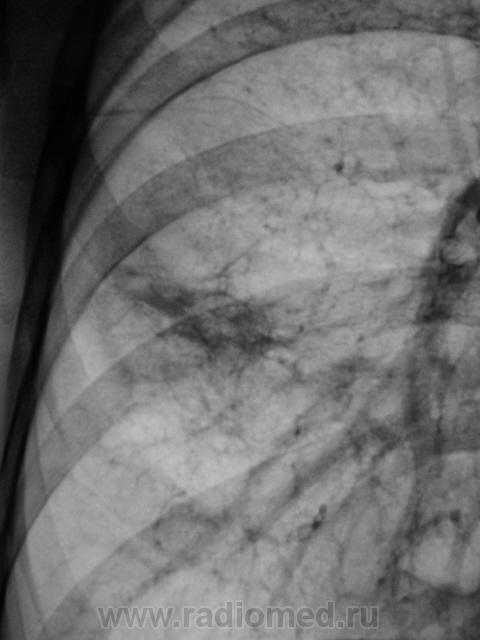

После лечения.

Предположу, не зная истории болезни. инфарктную пневмонию С4 сегмента справа.

не S4. Или ошибаюсь? Хорошая динамика.

По-моему, все-таки 4 сегмент.Междолевая прослеживается выше.

Средняя доля несколько уменьшена в размерах синдром средней доли на динамике отмечается Ро+ динамика с плеврокостальной реакцией. Передний ребернодиафрагмальный синус облитерирован.И смущает лишь один участок очень похож на полость с горизонтальным уровнем в правом кардиодиафрагмальном углу.